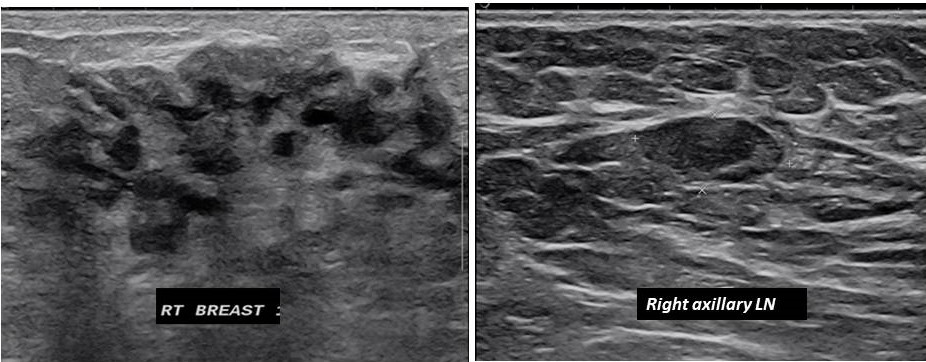

Full-field digital mammography (FFDM), bilateral CC and MLO view showed extremely dense breast tissue with no obvious abnormality [Figure 1]. Ultrasound (US) of the breast showed non-specific findings with non-circumscribed mixed echogenic area in the region of palpable lump at 12 o’clock, and a lymph node with eccentric cortical thickening in right axilla [Figure 2]. Subsequent US guided right axillary lymph node FNAC showed reactive hyperplasia. She was followed up after 3 months with persistence of her clinical symptom which was stable. This time she was evaluated with contrast enhanced mammography (CEM) which revealed heterogeneous non-mass enhancement in segmental distribution measuring 56 x 60mm in the central portion of right breast [Figure 3]. Pre-operative dynamic post contrast breast MRI showed nodular and clustered ring non-mass enhancement [Figure 4] in the similar distribution as in CEM. No other abnormality was seen in rest of the right breast and contralateral breast. US guided core needle biopsy of the right breast mass and the final histopathology of the mastectomy specimen yielded ductal carcinoma in situ (DCIS), solid type nuclear grade III without invasion [Figure 5]. Sentinel node biopsy was negative for malignancy.